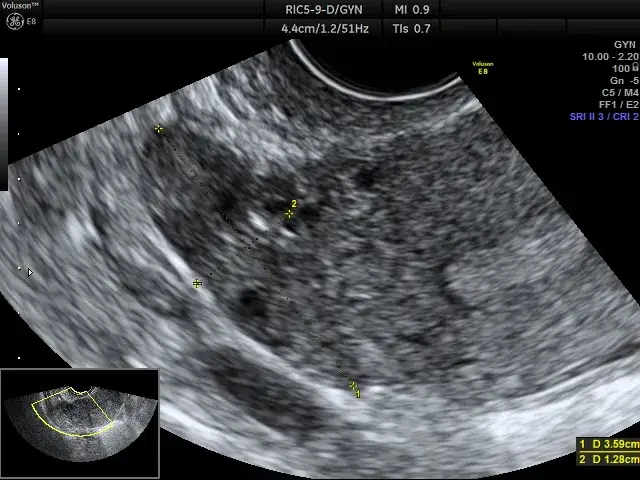

- Diagnostyka obejmuje USG przezpochwowe, a w razie potrzeby biopsję, histeroskopię lub wyłyżeczkowanie.

Podstawowym i niezwykle precyzyjnym badaniem, które pozwala na ocenę grubości endometrium, jest USG przezpochwowe. Dzięki niemu lekarz może dokładnie zmierzyć błonę śluzową macicy i ocenić jej strukturę, co jest pierwszym krokiem w diagnostyce wszelkich nieprawidłowości.

W przypadku, gdy wynik USG jest nieprawidłowy i sugeruje przerost, kolejnym krokiem jest często biopsja aspiracyjna endometrium. Jest to badanie mało inwazyjne, które zazwyczaj wykonuje się w gabinecie lekarskim. Polega ono na pobraniu niewielkiej próbki tkanki z jamy macicy za pomocą cienkiej rurki, co pozwala na ocenę mikroskopową endometrium.

W uzasadnionych przypadkach, gdy biopsja aspiracyjna jest niewystarczająca lub wynik jest niejednoznaczny, lekarz może zlecić dokładniejsze metody diagnostyczne. Należą do nich histeroskopia, czyli oglądanie wnętrza macicy za pomocą cienkiej kamery, z możliwością pobrania celowanego wycinka, oraz tradycyjne wyłyżeczkowanie jamy macicy, które pozwala na uzyskanie większej ilości materiału do badania histopatologicznego.